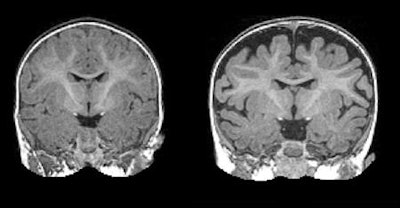

Using MR imaging, researchers have found that children diagnosed with autism at 2 years of age had a substantially greater amount of extra-axial cerebrospinal fluid (CSF) when they were 6 and 12 months old, according to a study published online March 6 in Biological Psychiatry.

The 6-month-old infants who eventually went on to develop autism had 18% more CSF than 6-month-olds who did not develop the condition. In addition, 6-month-old infants with CSF levels 24% greater than their counterparts went on to develop the most severe symptoms of autism. Those levels of CSF remained elevated when the subjects reached 12 and 24 months of age.

By using the elevated CSF as a benchmark, the researchers were able to predict with approximately 70% accuracy which babies would later be diagnosed with autism. While it is not a perfect predictor of autism, the differences in CSF are observable on a standard MRI scan.